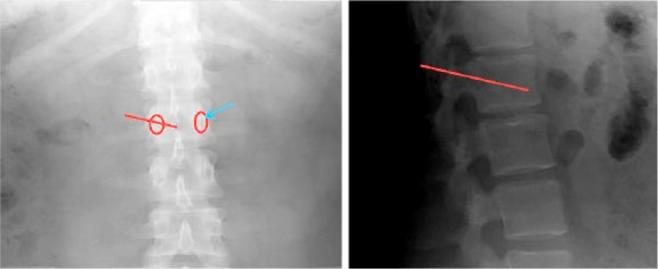

Thoracolumbar vertebral fracture incidents usually occur secondary to a high velocity trauma in young patients and to minor trauma or spontaneously in older people.Osteoporotic vertebral fractures are the most common osteoporotic fractures and affect one-fifth of the osteoporotic population.Percutaneous fixation by 'vertebroplasty' is a tempting alternative for open surgical management of these fractures.Despite discouraging initial results of early trials for vertebroplasty, cement augmentation proved its superiority for the treatment of symptomatic osteoporotic vertebral fracture when compared with optimal medical treatment.Early intervention is also gaining ground recently.Kyphoplasty has the advantage over vertebroplasty of reducing kyphosis and cement leak.Stentoplasty, a new variant of cement augmentation, is also showing promising outcomes.In this review, we describe the additional techniques of cement augmentation, stressing the important aspects for success, and recommend a thorough evaluation of thoracolumbar fractures in osteoporotic patients to select eligible patients that will benefit the most from percutaneous augmentation. A detailed treatment algorithm is then proposed. Cite this article: EFORT Open Rev 2017;2:293-299. DOI: 10.1302/2058-5241.2.160057.

胸腰椎骨折事件通常继发于年轻患者的高速创伤以及老年人的轻微创伤或自发发生。骨质疏松性椎体骨折是最常见的骨质疏松性骨折,影响五分之一的骨质疏松人群。“椎体成形术”经皮固定是这些骨折开放手术治疗的一种诱人替代方法。尽管椎体成形术早期试验的初步结果令人沮丧,但与最佳药物治疗相比,骨水泥强化已证明其在治疗有症状的骨质疏松性椎体骨折方面具有优越性。早期干预最近也越来越受到重视。后凸成形术比椎体成形术具有减少后凸和骨水泥渗漏的优势。支架成形术是骨水泥强化的一种新变体,也显示出有希望的结果。在本综述中,我们描述了骨水泥强化的其他技术,强调成功的重要方面,并建议对骨质疏松患者的胸腰椎骨折进行全面评估,以选择最能从经皮强化中获益的合格患者。然后提出了详细的治疗算法。引用本文:EFORT Open Rev 2017;2:293 - 299。DOI: 10.1302/2058 - 5241.2.160057。